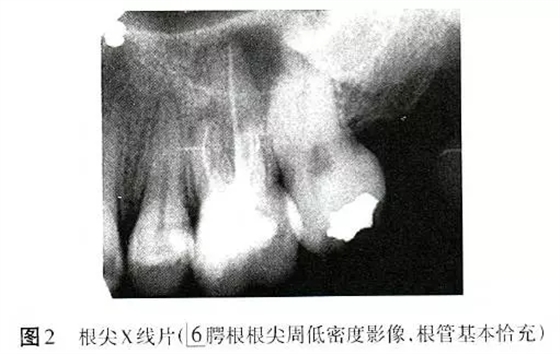

X線片顯示6根管恰充,腭根根尖周低密度影像,直徑6mm×6mm(圖2)。為排除根折,拍攝錐形束CT(CBCT),除發(fā)現(xiàn)MB2遺漏且未見明顯根折以外,意外發(fā)現(xiàn)6根尖周骨病損范圍遠較X線片所顯示的更廣,累及全部牙根,且患牙頰側(cè)硬骨板缺損(圖3)。診斷:6根管治療后疾?。╬ost-treatmentendodonticdisease,PTED)。